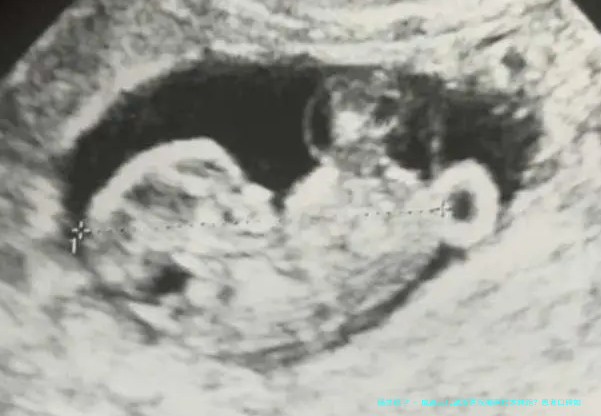

起先,这些医院普遍拥有尖端的实践室设备。例如,高清晰画质显微镜、镭射器、胚胎培育系统等,这些配备能够为医生提供愈发精准、愈发安全的操作环境,进而提高试管婴儿的成功率。

第二,各大医院在三代试管婴儿技术方向选用了多种前沿技术。如胚胎移植前基因诊断(PGD)和胚胎移植前遗传学检查筛选(PGS)等,这一些技术能够对胚胎进行全面的遗传学检测,有效降低遗传病症的风险。